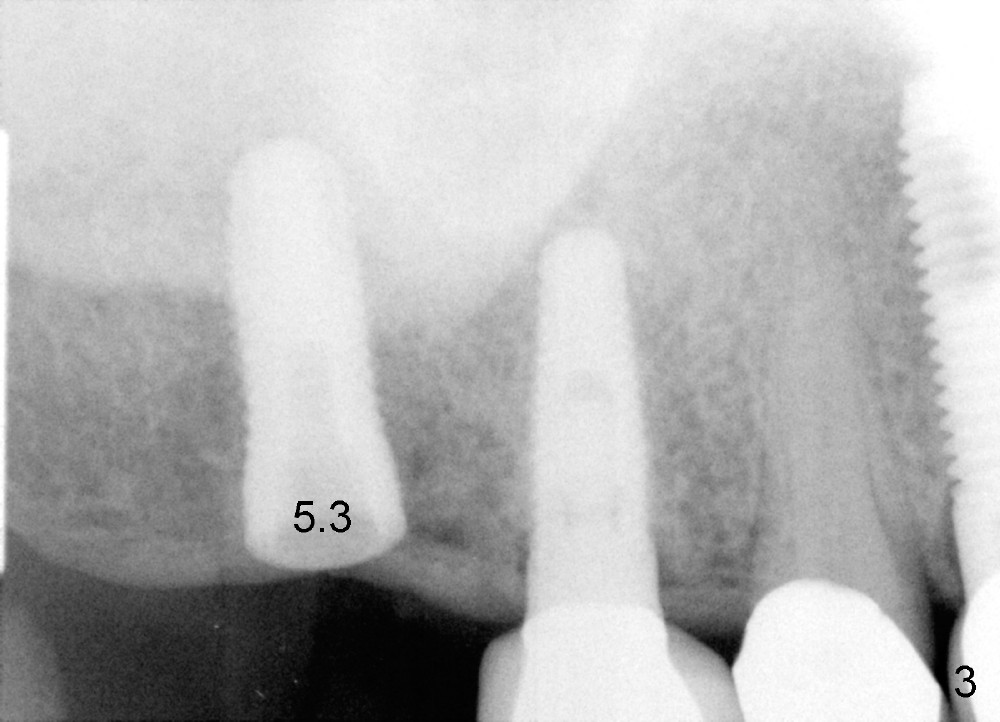

Analysis of preop PA suggests that the density of the cancellous bone is low at the site of the tooth #2. It is confirmed when a 2 mm pilot drill is used to initiate osteotomy. There is no drilling resistance once the pilot drill penetrates the cortex. A parallel pin is inserted for trajectory (Fig.1: P; 8 mm deep). The osteotomy is slightly moved distally with Lindermann bur and enlarged by inserting Bone Expanders from 2.6 to 3.8 mm at the depth of 12 mm (Fig.2). The osteotomy is then intended to move mesially and the depth is increased to 14 mm. Finally a 5.3x14 mm submerged implant is placed with insertion torque ~ 40 Ncm (Fig.3). The implant looks to have been tightly engaged into the bone (Fig.4). In one word, minimal bone removal is required for implant placement in the soft bone, particularly in the maxillary posterior region. A 8.2 mm healing abutment is placed; the flaps are closed by Chromic gut suture and perio glue (Fig.5). The wound heals normally 1 week postop (Fig.6). Fig.7 shows X-ray 3 months postop (H: healing abutment). Soft tissue looks healthy 4 months postop before (Fig.8) and after (Fig.9) removal of the healing abutment for restoration. There is no bone loss 7 months post cementation and 11 months postop (Fig.10 C: crown). It appears that bone expansion prevents bone resorption. There is no bone resorption 1 year 9 months post cementation. The implant is functioning 3 years 9 months post cementation (Fig.11).